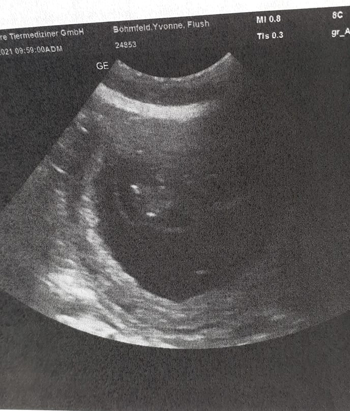

22.02.2021 W-underkinder in Sicht Beim heutigen Trächtigkeitsultraschall, der Corona bedingt anders war als gewohnt (ich musste Flusi im Behandlungszimmer abgeben denn der Ultraschallraum ist zu klein für Abstand), zeigten sich unsere kleinen W-under auf Anhieb. |